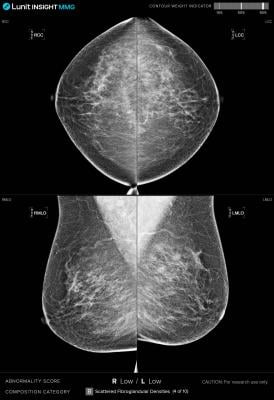

Lunit's AI Solution Enhances Qatar's National Breast Cancer Screening Program

Middle East's first full-scale AI adoption for national screening marks Lunit's latest milestone amid rapid expansion of global cancer screening initiatives